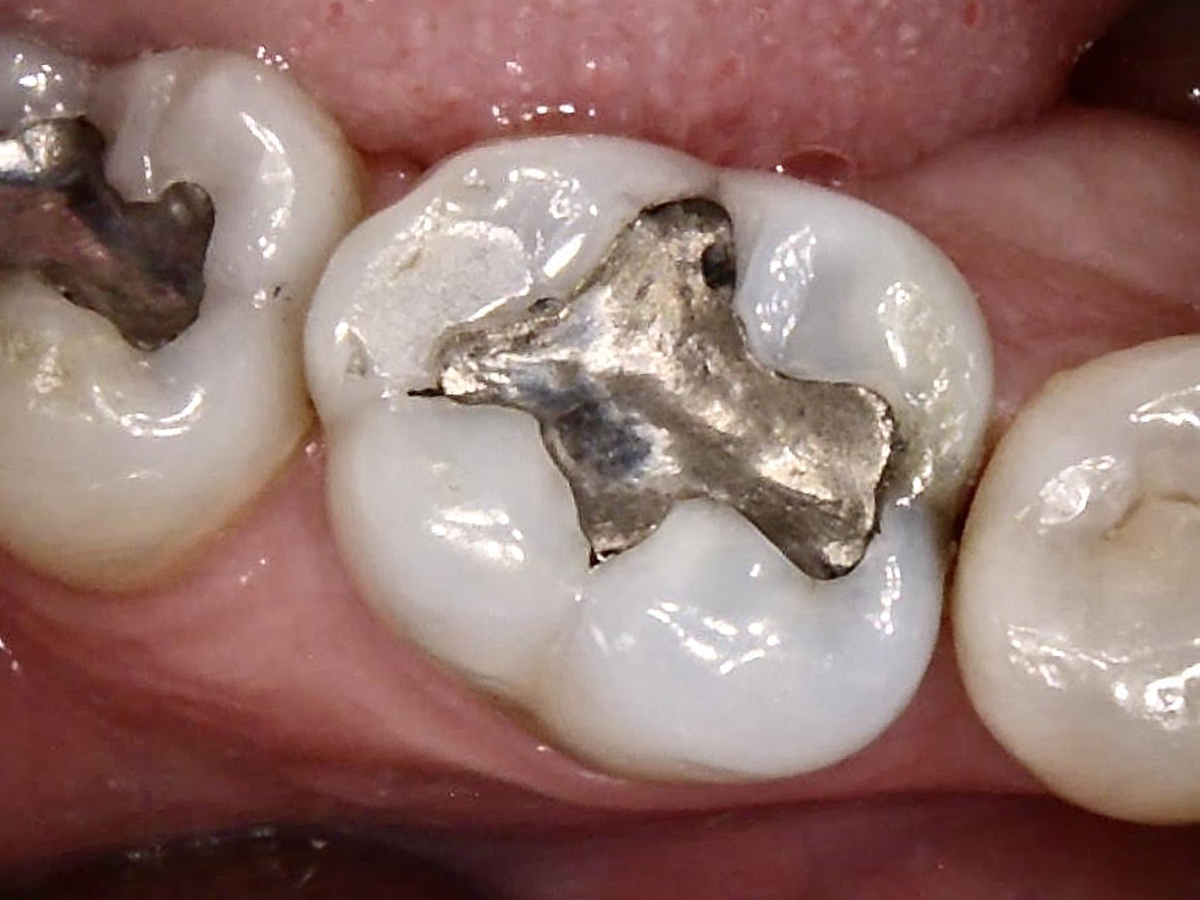

Fig 1. Tooth No. 30, preoperative.

Figure 1

The benefits and ease of a universal bonding agent are demonstrated through the following case example of a Class II restoration. The patient was a 56-year-old woman. At her initial examination, it was observed that her lower right first molar (tooth No. 30) had an old failing amalgam restoration on the occlusal and a mesial fracture line with clinically visible caries (Figure 1). The preoperative bitewing x-ray did not show any mesial caries. The tooth needed a new restoration. The treatment plan was to perform a mesial-occlusal composite filling. A bitewing and periapical x-rays were taken to make sure that there was no other interproximal caries or any periapical lesion. Furthermore, an intraoral photograph taken with an intraoral camera was used to present and to help confirm the caries.